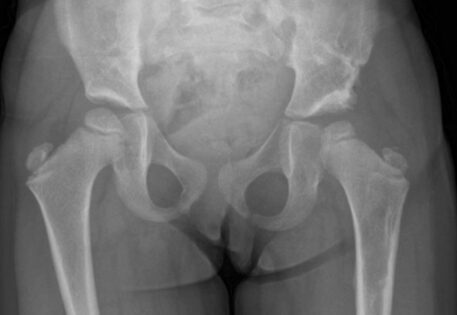

Hip dysplasia can manifest in various syndromes, including Prader-Willi syndrome, arthrogryposis, caudal regression syndrome, and Kabuki syndrome. Syndromic hip dysplasia cases in Dubai often involve more pronounced anatomical distortions, posing greater challenges in treatment and higher recurrence risks. Dr. Qureshi, a child orthopaedic doctor in Dubai, is experienced in addressing these complex cases, providing specialised care and management for each unique condition.

Dr. Qureshi has successfully managed numerous cases of syndromic hip dysplasia, employing investigations such as arthrography and CT imaging to assess reconstruction feasibility and plan surgical interventions. The treatment strategy is customarily crafted as a tailored combination of different techniques to address distinct components and contributory factors contributing to the dislocation.